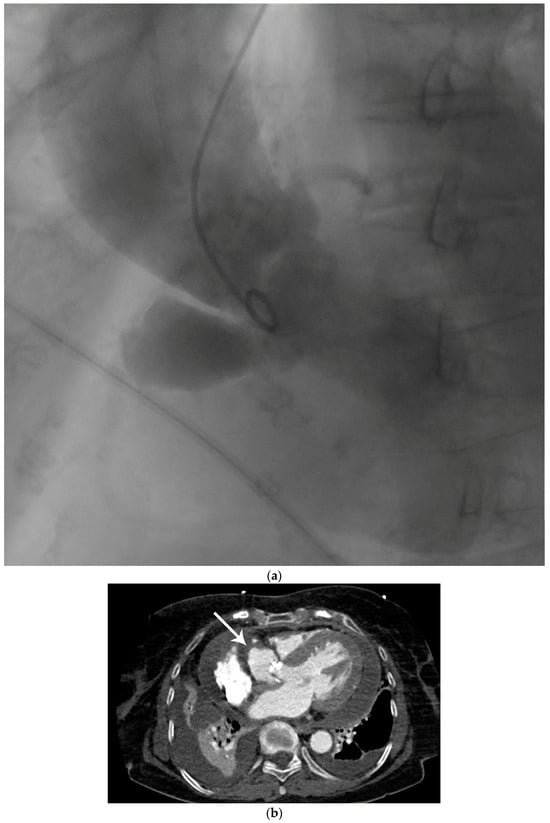

Figure 1. Preoperative diagnostic imaging of an 83-year-old female patient presenting with progressive symptomatic aortic valve stenosis. (a) Preoperative laevocardiography showed a para-aortic contrast media deposition. The cavity showed a wide base and was in continuity with the left ventricle. In this case, the initial diagnosis was made during standard laevocardiography. This allows for direct identification of the primary entry site and connection of the cavity, which is an important factor during differential diagnosis. If the initial diagnosis is made with other modalities such as echocardiography, the entity and connection of pericardiac and periaortic lesions may be more difficult. As an example, Emmert et al. reported a case of a chronic subannular abscess that was misdiagnosed for a sinus of Valsalva aneurysm and was only diagnosed correctly during intraoperative exploration [1]. Thus, live transcatheter contrast imaging as performed here can help to avoid incorrect preoperative diagnosis and preparation. In this case, preoperative echocardiography remained inconclusive with respect to the suspected lesion, although transthoracic or transesophageal echocardiography is widely accepted as the primary imaging method for infectious cardiac diseases [2,3]. In this selected patient group, in which the topographic anatomy remains unclear in other imaging modalities, laevocardiography may provide critical additional information for planning of the procedure. However, the risk of embolization associated with catheterization must be taken into account, particularly in the case of larger vegetations. (b) To confirm the initial preliminary diagnosis, contrast-enhanced computed tomography was utilized. Computed tomography, or cardiac magnetic resonance imaging, has increasingly become the gold standard for the imaging of more complex complications of infective cardiac diseases [4]. The main advantage of this imaging technique is the three-dimensional visualization of the cavity dimensions and connections. For this, electrocardiographic gating during computed tomography is recommended to avoid artifacts. In this horizontal plane of the computed tomography imaging of our patient, the wall of the spurious aneurysm was thickened (arrow), which may correspond to partial mural thrombosis or post-infective morphologic changes. In this context is should be considered that aortic subannular abscess-like formations can arise not only from infective endocarditis, but may also result from non-infective inflammatory lesions such as Libman–Sacks endocarditis, as reviewed by Murillo et al. [4]. Additionally, left ventricular hypertrophy, pericardial effusion, and pleural effusion were apparent in computed tomography imaging, indicating the beginning of cardiac decompensation. (c) In the frontal plane, the connection of the abscess cavity to the left ventricular outflow tract was visualized. Heavy calcification not only of the aortic valve but also of the base of the pseudoaneurysm was noted. Additionally, the aneurysmatic dilatation of the ascending aorta, which most likely resulted from the chronic aortic stenosis as a poststenotic aneurysm, can be seen in this plane. In prior studies, this poststenotic dilatation has been described for aortic stenosis, especially when the aortic valve is bicuspid [5]. (d) Three-dimensional reconstruction of the suspected lesions may be of great interest for operative planning, since this technique allows for the visualization of the local topography of the target lesion. In this case, the close topographic proximity of the abscess excavation to the right coronary artery became apparent (arrow). With ever improving rendering and electrocardiographic gating techniques, contrast-enhanced computed tomography has evolved into a powerful diagnostic tool in the preoperative planning for complex cardiac malformations [6].